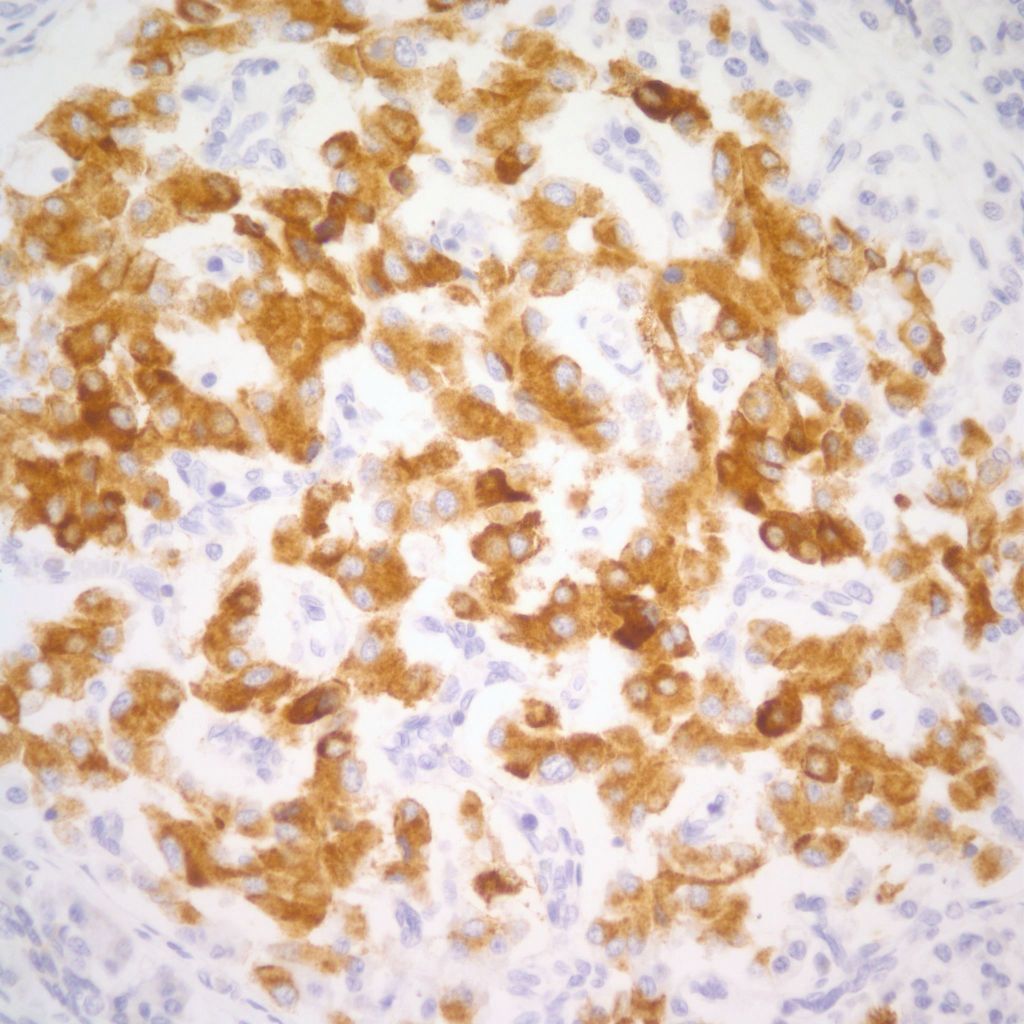

However, islet cell type and distribution in the pancreas is not homogenous throughout the organ and also changes with gestation. An increase in islet area may be difficult to determine without quantitative technique and comparison with matched controls for gestation and location within the pancreas. Beta cells that secrete insulin and amylin, normally make up greater than a majority of cells in an islet. Therefore, the percentage of beta cells in an islet is seldom helpful determining an overall hyperplasia of insulin secreting cells. A more reliable feature to identify evidence of increased islet response is cell hypertrophy. These hypertrophic cells are polyploid with clearly enlarged nuclei compared to surrounding cells (Fig 6).

The cytomegalic cells can be identified even with marked autolysis of the pancreas (fig 7).

The hypothesis is that both hyperplasia and polyploid cell hypertrophy are adaptations to increase insulin secretion. An anti-insulin immuno-stain can confirm the identity of cytomegalic cells as insulin staining and help to visually demonstrate the size and extent of islets in general.